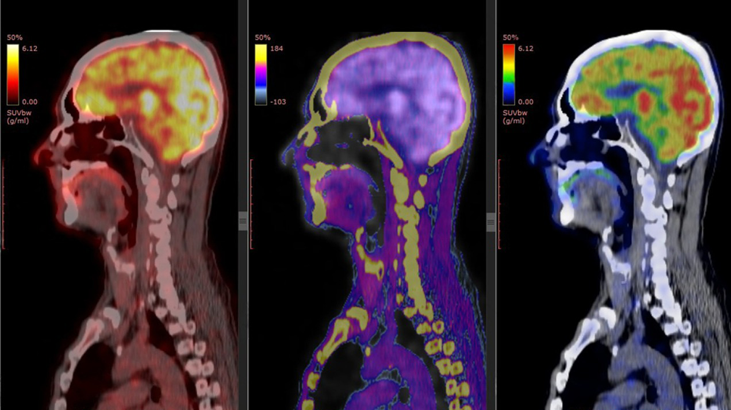

NEUROLOGÍA

¿Qué es un PET/CT?

La Tomografía por Emisión de Positrones (PET) combinada con la Tomografía

Computarizada (CT) es la técnica más avanzada para evaluar la actividad metabólica y la anatomía de órganos y tejidos en una sola exploración.

Permite detectar enfermedades en fases tempranas, monitorizar tratamientos y planificar intervenciones de manera segura y precisa.

Nuestro equipo: Siemens Biograph Trinion

En la Clínica de Marly contamos con el Siemens Biograph Trinion, un equipo de última generación que se destaca por:

El Biograph Trinion representa uno de los estándares tecnológicos más avanzados en diagnóstico PET/CT a nivel mundial, respaldado por la innovación y experiencia de Siemens Healthineers.